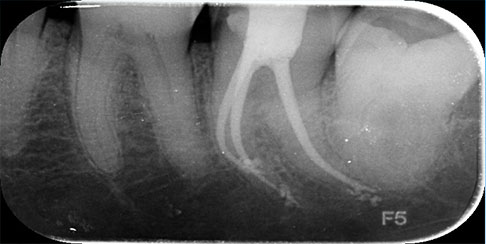

Digital X-Rays

Digital dental x-rays emit minimal amounts of radiation so they are extremely safe. All our five operatories have the latest digital x ray units for smooth functioning and flawless treatment for our patients.